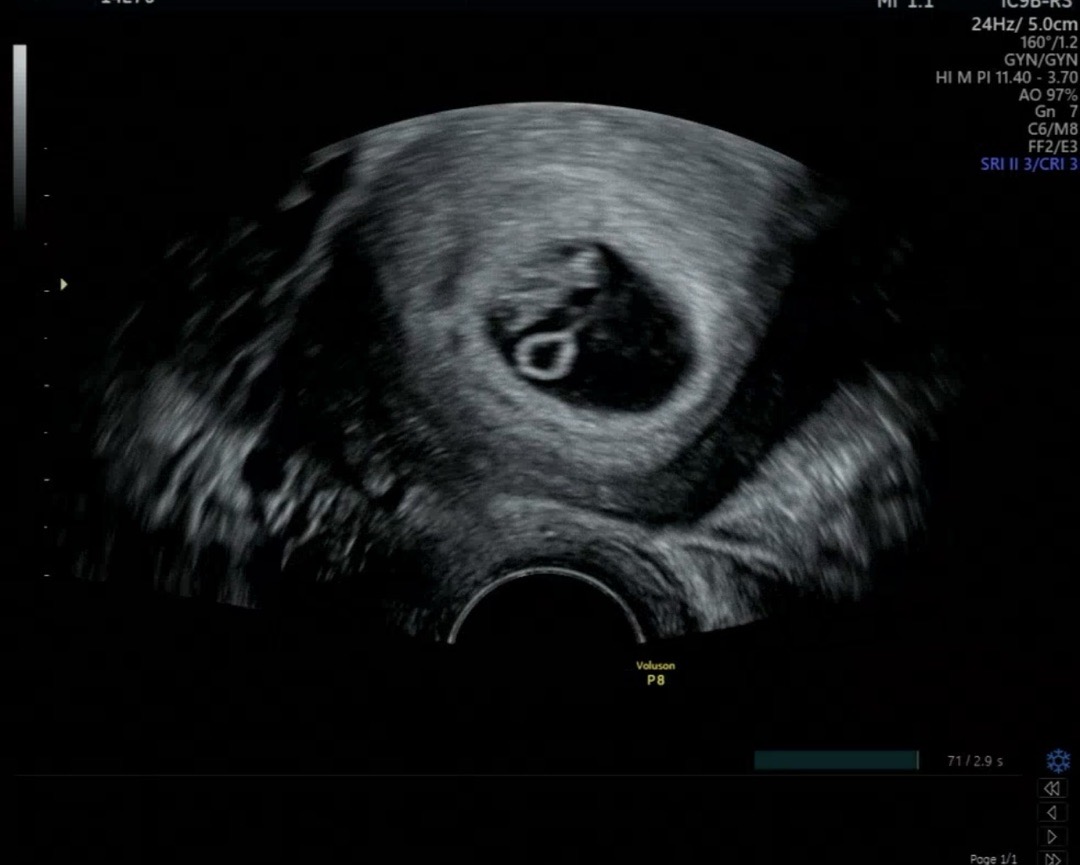

7주 0일차 아기집

오늘 춈파 봤더니 난황도 보이고 미세하게 양막도 보이더라고요. 신기하네요! 지난주에 갔을 때 아기집이 약간 납작한 타원형이라서 걱정했는데 아기집이 동그래져서 안심했네요! CTL 1.3cm 심장박동수 174bpm나왔어요